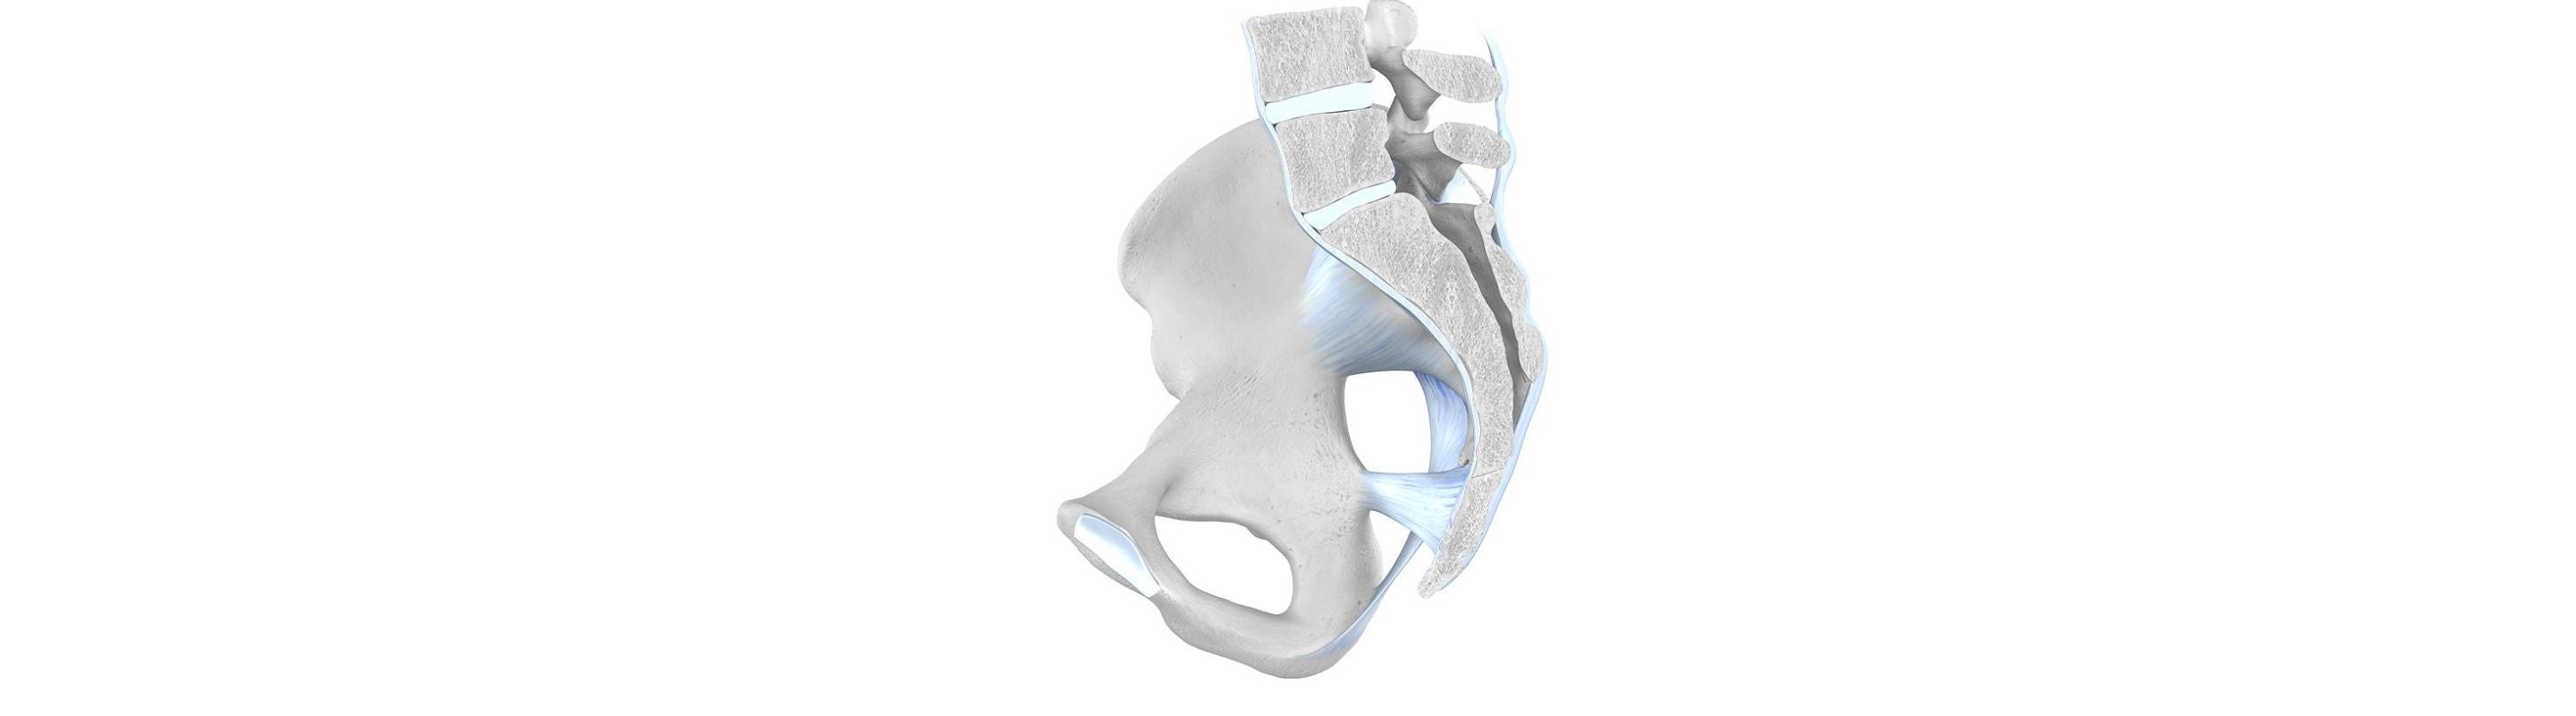

The lumbar region of the back is instrumental in providing stability and facilitating the transfer of power to the lower body. It allows for complex movements like bending, walking and running. Overexertion and poor proprioception often lead to patients experiencing pain in the lower back area, also known as lumbar pain.

Low Back Pain Causes

There are several factors that can cause pain in the lower back. Some of them include:

- Lumbago – pain in the surrounding muscles and joints of the lower back

Long-term neglect and degeneration of the lower back can lead to chronic lower back pain. A patient can sometimes experience pain for more than 12 consecutive weeks.